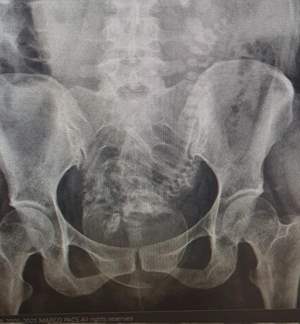

بچه ها شاید باورتون نشه یدفه یه خانم خیلی معمولی ۲۸ ساله با شکایت یبوست و دل درد اومد

با شک به انسداد فرستادمش گرافی

وقتی عکسشو میدیدم و تحلیل میکردم چرا تو لگنش توپ هست دوزاریم افتاد خانم در حال زایمانه و فکر میکنه اون زوری که میزنه بخاطر یبوسته!

نمیدونست بارداره و نیم ساعت بعدش زایید🥲